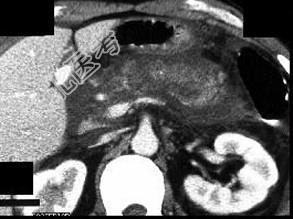

- 单项选择题女,45岁, 急性上腹部持续性疼痛10小时,程度剧烈, 放射到胸背部,恶心、呕吐, 白细胞计数增高,血尿淀粉酶升高, 影像所见如图,最可能的诊断是 ( )

A、急性单纯性胰腺炎

B、急性出血坏死性胰腺炎

C、慢性胰腺炎

D、胰腺癌

E、胰腺脓肿